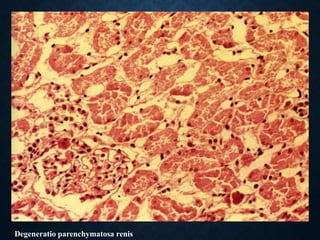

WATER ACCUMULATION

• Disturbance of the water content of the cell is

indicated as cloudy swelling or parenchymatous

degeneration.

• Disturbance of the amount of water in the cell can be

manifested as:

• edema cells

• vacuolar degeneration

• hydrops degeneration

MICROSCOPICALLY

• transparent cytoplasm

• indistinct cell membrane

• loss of nucleus

Degeneratio parenchymatosa renis